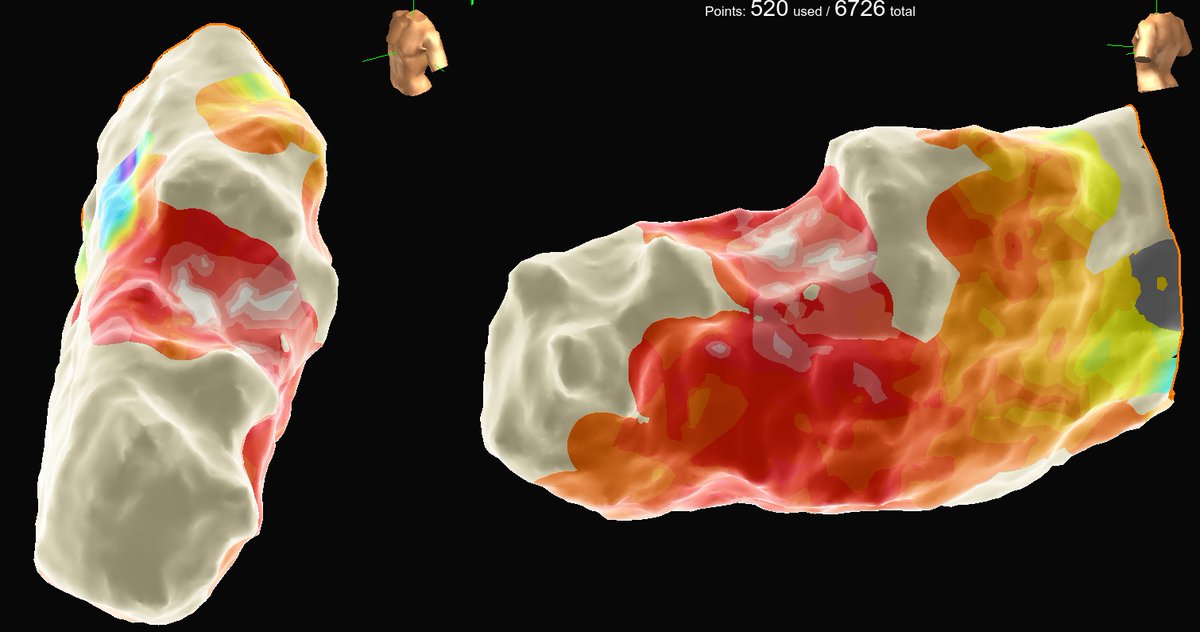

Volt released some pretty impressive 12 month data with over 80% success in paroxysmals and excellent persistent AF results. Read the simultaneous publication! kwnsfk27.r.eu-west-1.awstrack.me/L0/https:%2F%2…